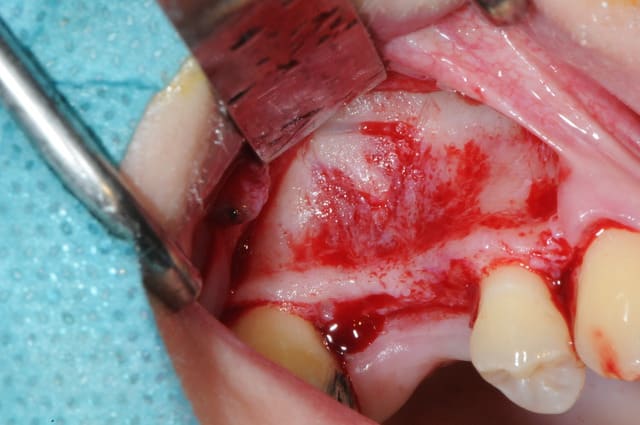

- mise en place de l'implant

- séchage discret de la surface osseuse

- injection du Vital Os en palatin et partout autour de l'implant

- hé hé hé ... pas de membrane de recouvrement, le matériaux se suffit à lui même. d'où une petite économie substantielle pour ceux qui ont l'habitude de mettre systématiquement une membrane après un Caldwell-Luc.

- sutures...